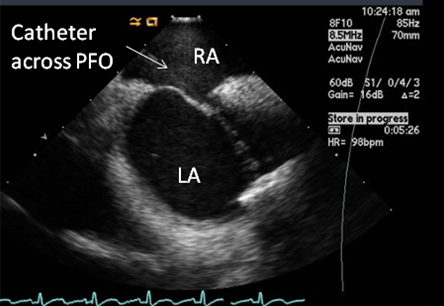

Not routinely used as a diagnostic procedure for PFO because of its high cost.

Performed in conjunction with percutaneous closure of PFO.[21]

Advantage is elimination of need for deeper sedation and discomfort associated with a transesophageal echo.[Figure caption and citation for the preceding image starts]: Intracardiac echo showing a catheter placed across the PFO into the left atriumFrom the collection of Kul Aggarwal, MD [Citation ends].com.bmj.content.model.Caption@a86e958

visualization of PFO